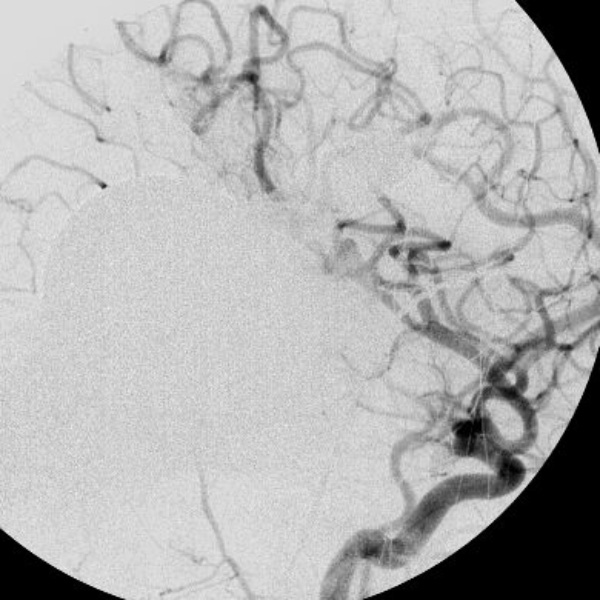

No.359 モニタリング

No.359 手術前

No.359 手術中

No.359 手術後

出血既往があり。2回の手術前血管内手術の後に、

Lateral transpeduncular approachにより再々出血予防を目的に

摘出手術を行う。完全摘出であることを確認した。

手術による合併症や後遺症なしで退院した。経過良好。